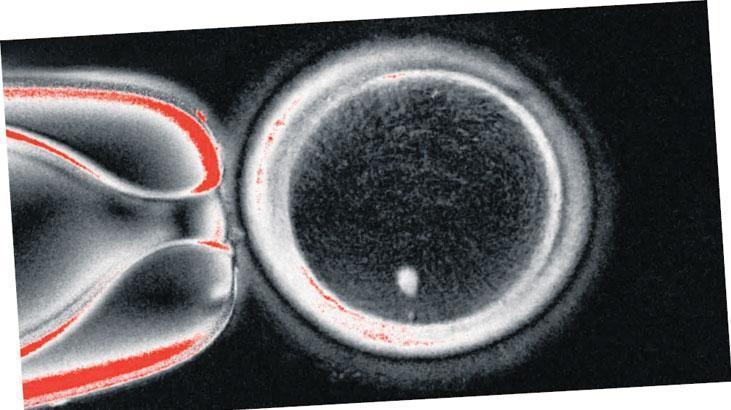

ABD’de kısırlığa çare olarak yeni bir yöntem geliştirildi. Oregon Sağlık ve Bilim Üniversitesi’nde insanların deri hücrelerinden alınan DNA’ların işlemden geçirilmesiyle yumurtalar elde edildi. In vitro gametogenez (IVG) denilen bu yöntemle “oosit” denilen 82 adet yumurta oluşturuldu. Bu yumurtalar, tüp bebek yöntemiyle (IVF) laboratuvarda spermlerle döllendirildi. Böylece yaşamın başlangıcı olan embriyolar oluştu. Altı gün sonra embriyoların yüzde dokuzu, IVF işlemi için rahime transfer edilebilecek kadar gelişti. Ancak embriyolarda bir dizi anormallik görülünce deney sonlandırıldı. Çalışmada, 1996’da Dolly adlı koyunun klonlanmasında kullanılan yöntemden faydalanıldı. Araştırmacılar, bu teknikle vücuttaki hemen her hücrenin çocuk dünyaya getirmek için kullanılabileceğini söyledi. Deneyler devam ederken yöntemin gerçek hayatta uygulanmasının 10 yılı bulabileceği belirtildi.

Yeni geliştirilmekte olan yöntemle yaşlılık veya hastalıktan kaynaklanan kısırlığın üstesinden gelinebileceği bildirildi. Çalışmayı yapan ABD’deki Oregon Sağlık ve Bilim Üniversitesi Embriyonik Hücre Merkezi Direktörü Prof. Shoukhrat Mitalipov, “İmkansız sanılan bir şeyi başardık” dedi. Mitalipov, “Hedefimiz yöntemi kusursuz hale getirmek. Geleceğin bu yönde ilerleyeceğini düşünüyorum. Çünkü çocuk sahibi olamayanların sayısı artıyor. In vitro gametogenez denilen bu teknoloji, vücut dışında sperm ve yumurta üretmeyi hedefliyor. Amaç kullanabilecekleri spermleri veya yumurtaları olmayan kişilerin çocuk sahibi olmasını sağlamaktır” diye konuştu.